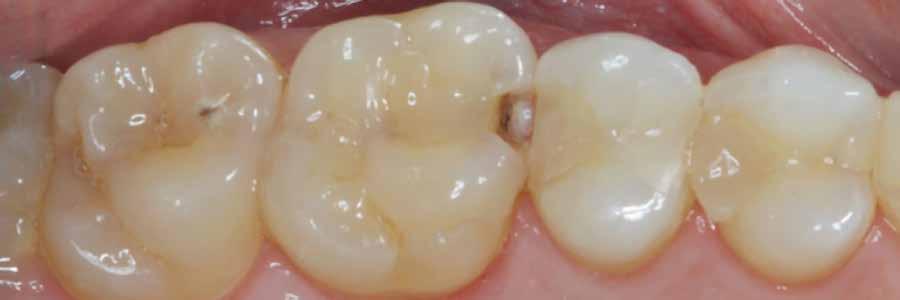

12. ábra: A premoláris fogak preoperatív állapota.

13. ábra: A premoláris fogak postoperatív fotója.